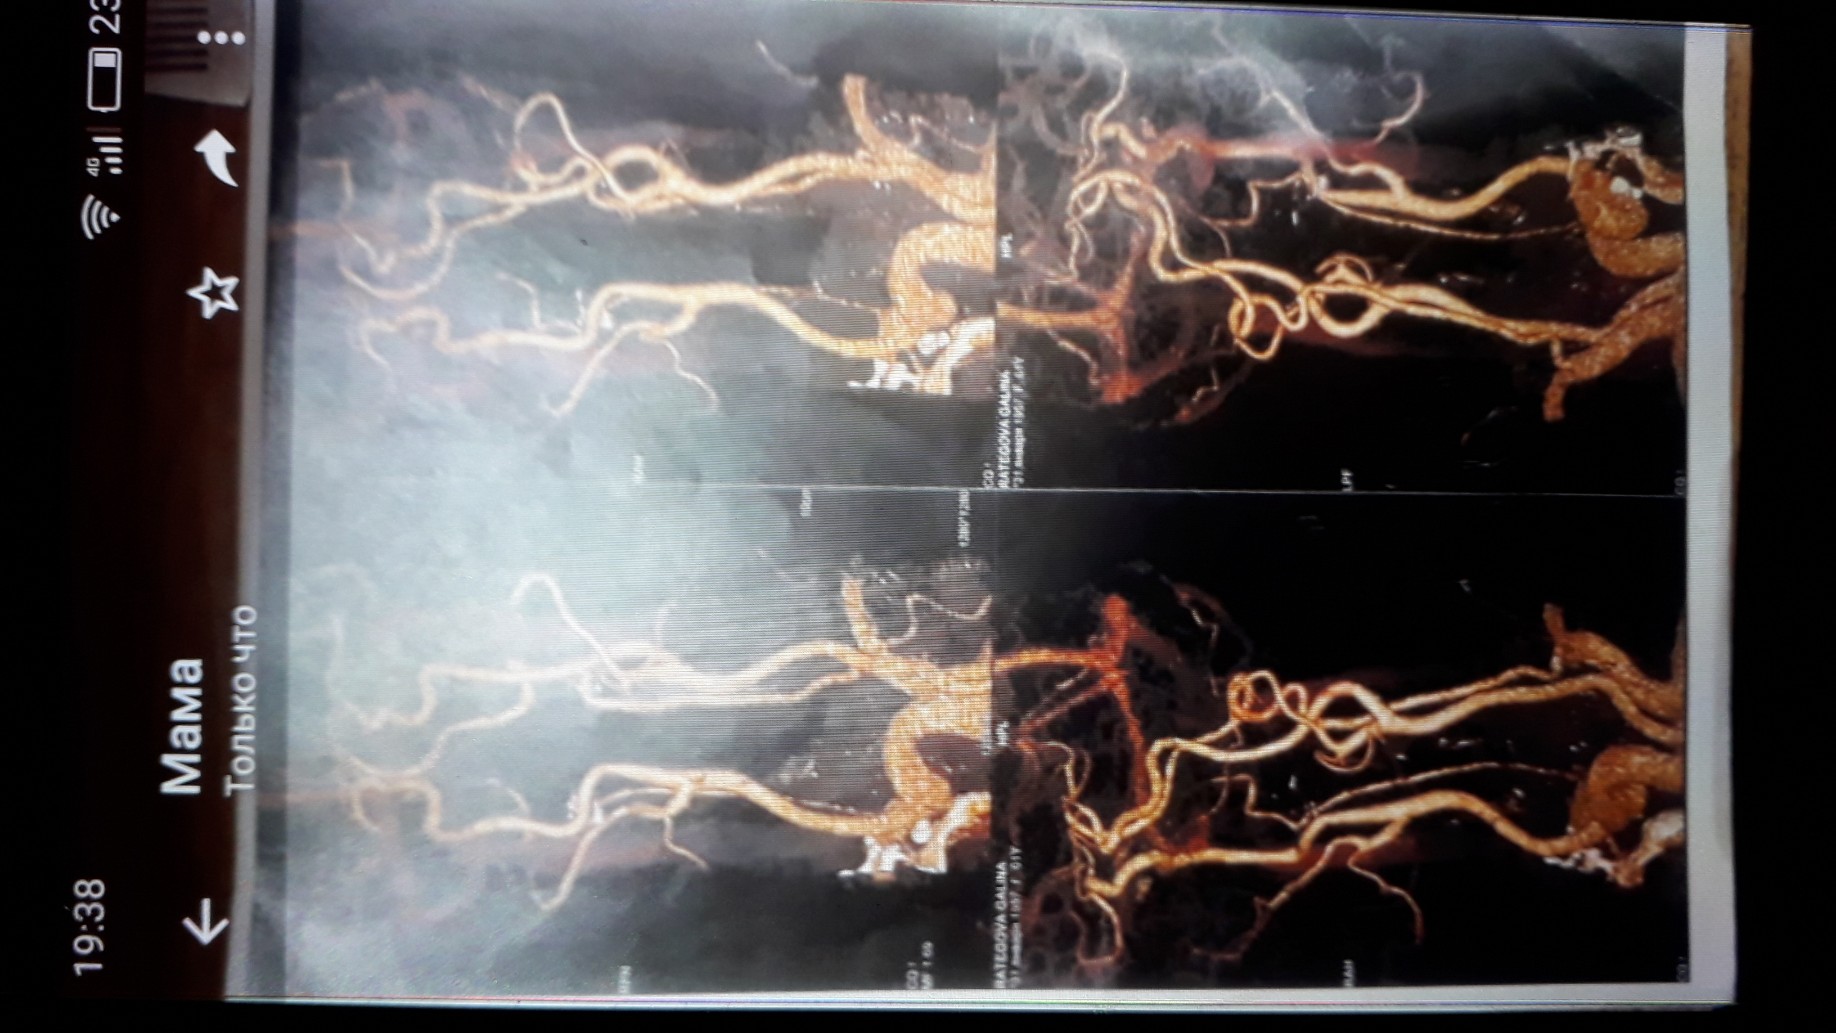

Если есть, то мне нужно заключение, а лучше просто фото протокола сосудов. Я посоветуюсь с сосудистыми хирургом и вам напишу.

До коллеги еще не добралась, поэтому с расшифровкой чуть попозже скажу, вы это исследование только год назад делали, больше не повторяли? И еще раз напишите, что именно вы принимали, какие уколы делали. В том числе то, что назначали вам другие врачи